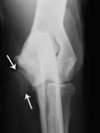

Q

Avulsed olecranon (fracture)